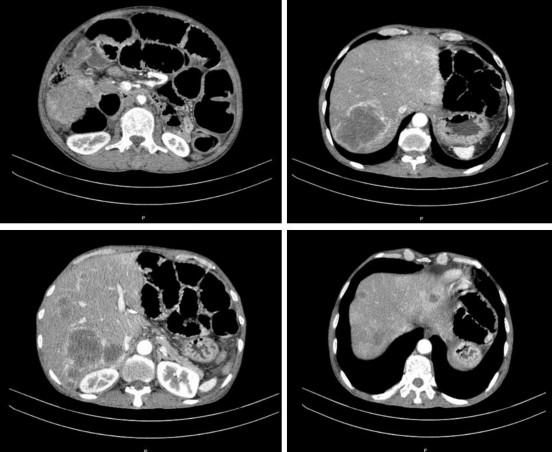

- Cắt lớp vi tính ổ bụng

Kết quả:

Dày thành đại tràng góc gan trên đoạn dài 52mm, vị trí dày nhất ~ 17mm, sau tiêm ngấm thuốc mạnh, giãn đoạn đại tràng lên và ruột non trước tổn thương

Gan: kích thước bình thường, bờ không đều. Nhu mô gan hai bên có các nốt và khối tổn thương, giảm tỷ trọng trước tiêm, sau tiêm ngấm thuốc viền mạnh. Khối lớn kích thước 67 x 70 mm.

Dịch tiểu khung dày nhất 17mm.